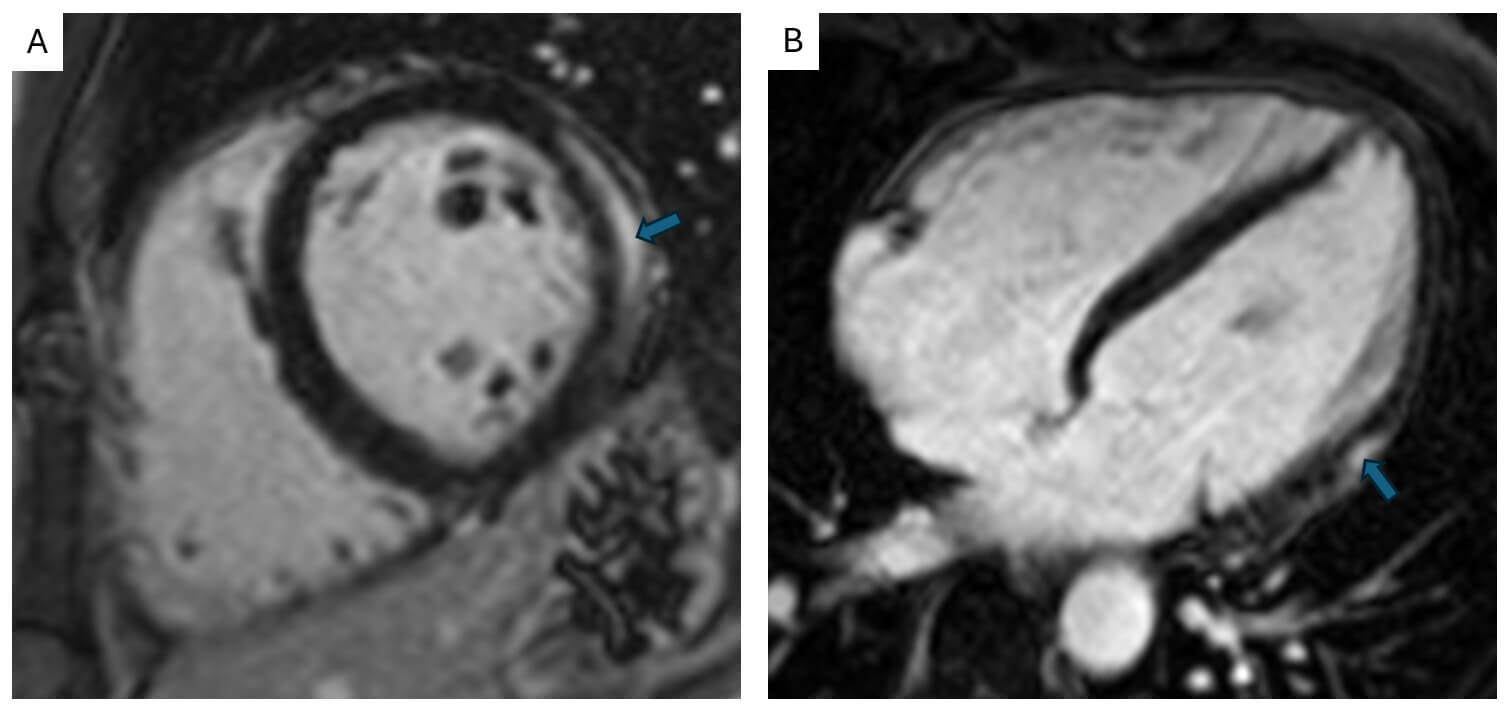

Late gadolinium enhancement (LGE) uses T1-weighted inversion-recovery sequences following gadolinium contrast administration. It identifies focal areas of predominantly myocardial necrosis and fibrosis. In myocarditis, LGE typically appears in subepicardial or mid-wall patterns, often in the inferior/inferolateral segments of the left ventricle (Fig. 3). While signal intensity often diminishes in chronic stages, persistent LGE related to the formation of scar, making it the most reliable indicator of myocarditis in approximately 90% of cases [32], and a valuable marker for long-term prognosis, where presence of LGE in viral myocarditis, is associated with 8.4-fold increase in all-cause mortality, after adjusting for left ventricular function, New York Heart Association (NYHA) functional class and left ventricle end diastolic volumes [33].

Fig. 3.

Cardiac magnetic resonance late enhancement imaging. Cardiac MRI mid short-axis (A) and four-chamber (B) images demonstrating post-gadolinium mid to subepicardial enhancement in the lateral wall (arrows). Images acquired on Siemens Aera 1.5T scanner (Siemens, London, England).